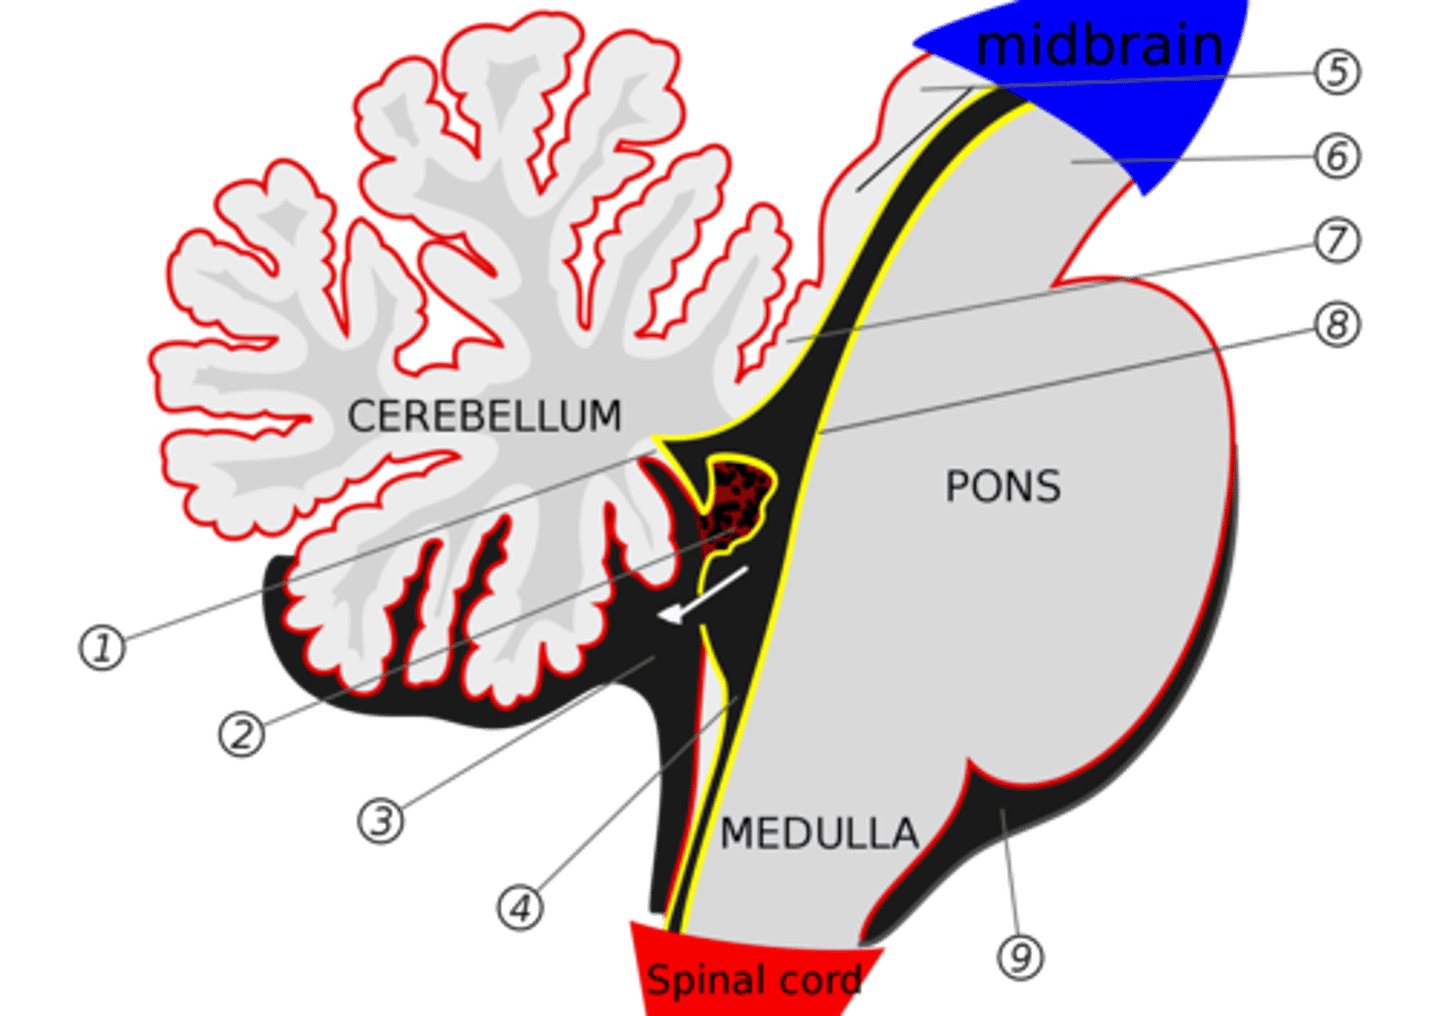

What are the structures of the brainstem?

1. mesencephalon (midbrain)

2. pons

3. medulla oblongata

What is the tectum?

roof of the midbrain

What is the tegmentum?

floor of midbrain

What are the fibers of the tegmentum?

ascending fibers

What is the crus cerebri?

part of the cerebral peduncles which contain descending tracts

What are the fibers of the crus cerebri?

descending fibers

What leaves the peduncular fossa?

CN III

What notable structures are on the dorsal surface of the mesencephalon (tectum)?

1. superior colliculi (right and left)

2. inferior colliculi (right and left)

image -- 5

What other notable structure should you see if you see two red nuclei?

"if you see two red nuclei you're at the superior colliculus level"

Where does CN III exit the brainstem?

interpeduncular fossa (ventral surface)

Where does CN IV exit the brainstem?

inferior colliculus (dorsal surface)

exits dorsal + caudal (posteroinferior) to nucleus

Where are the CN III and IV nuclei?

tegmentum mesencephalon

CN III -- anterosuperior

CN IV -- posteroinferior

What is the floor of the 4th ventricle?

tegmentum pons

What is the superior medullary velum?

membrane that forms the superior portion of the 4th ventricle roof

image -- 7

What is the inferior medullary velum?

membrane that forms the inferior portion of the 4th ventricle roof

image -- 1